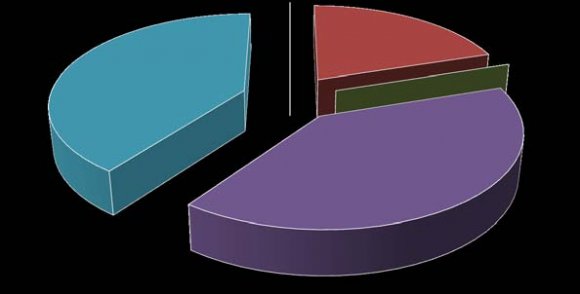

The highest number of studied cases belonged to 50-59 year age range with 31.25%, and male to female ratio of 1:1.14. The second highest studied range is 40-49years (29%) with male to female ratio of 1:0.4. The commonest pathology is disc hernia, 16 cases (33.3%) with male to female ratio of 3:1. Spondylosis without any evidence of disc hernia was high with 12 cases (25%). 62.5% of herniated disc occurred at L4/L5 disc level followed by 25% at L5/S1 disc level. At L4/L5 level male to female ratio is 4:1 while it is 1: